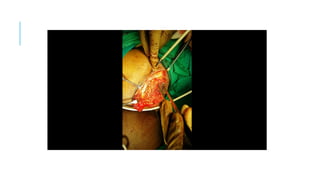

THE COURSE OF TREATMENT

Embolization of pelvic AVM done

>95% flow reduction achieved

Plan for excision of AVM in right

gluteal region done under general

anaesthesia after taking high risk

consent and consent for colostomy

THE COURSE OFTREATMENT Embolization of pelvic AVM done >95% flow reduction achieved Plan for excision of AVM in right gluteal region done under general anaesthesia after taking high risk consent and consent for colostomy